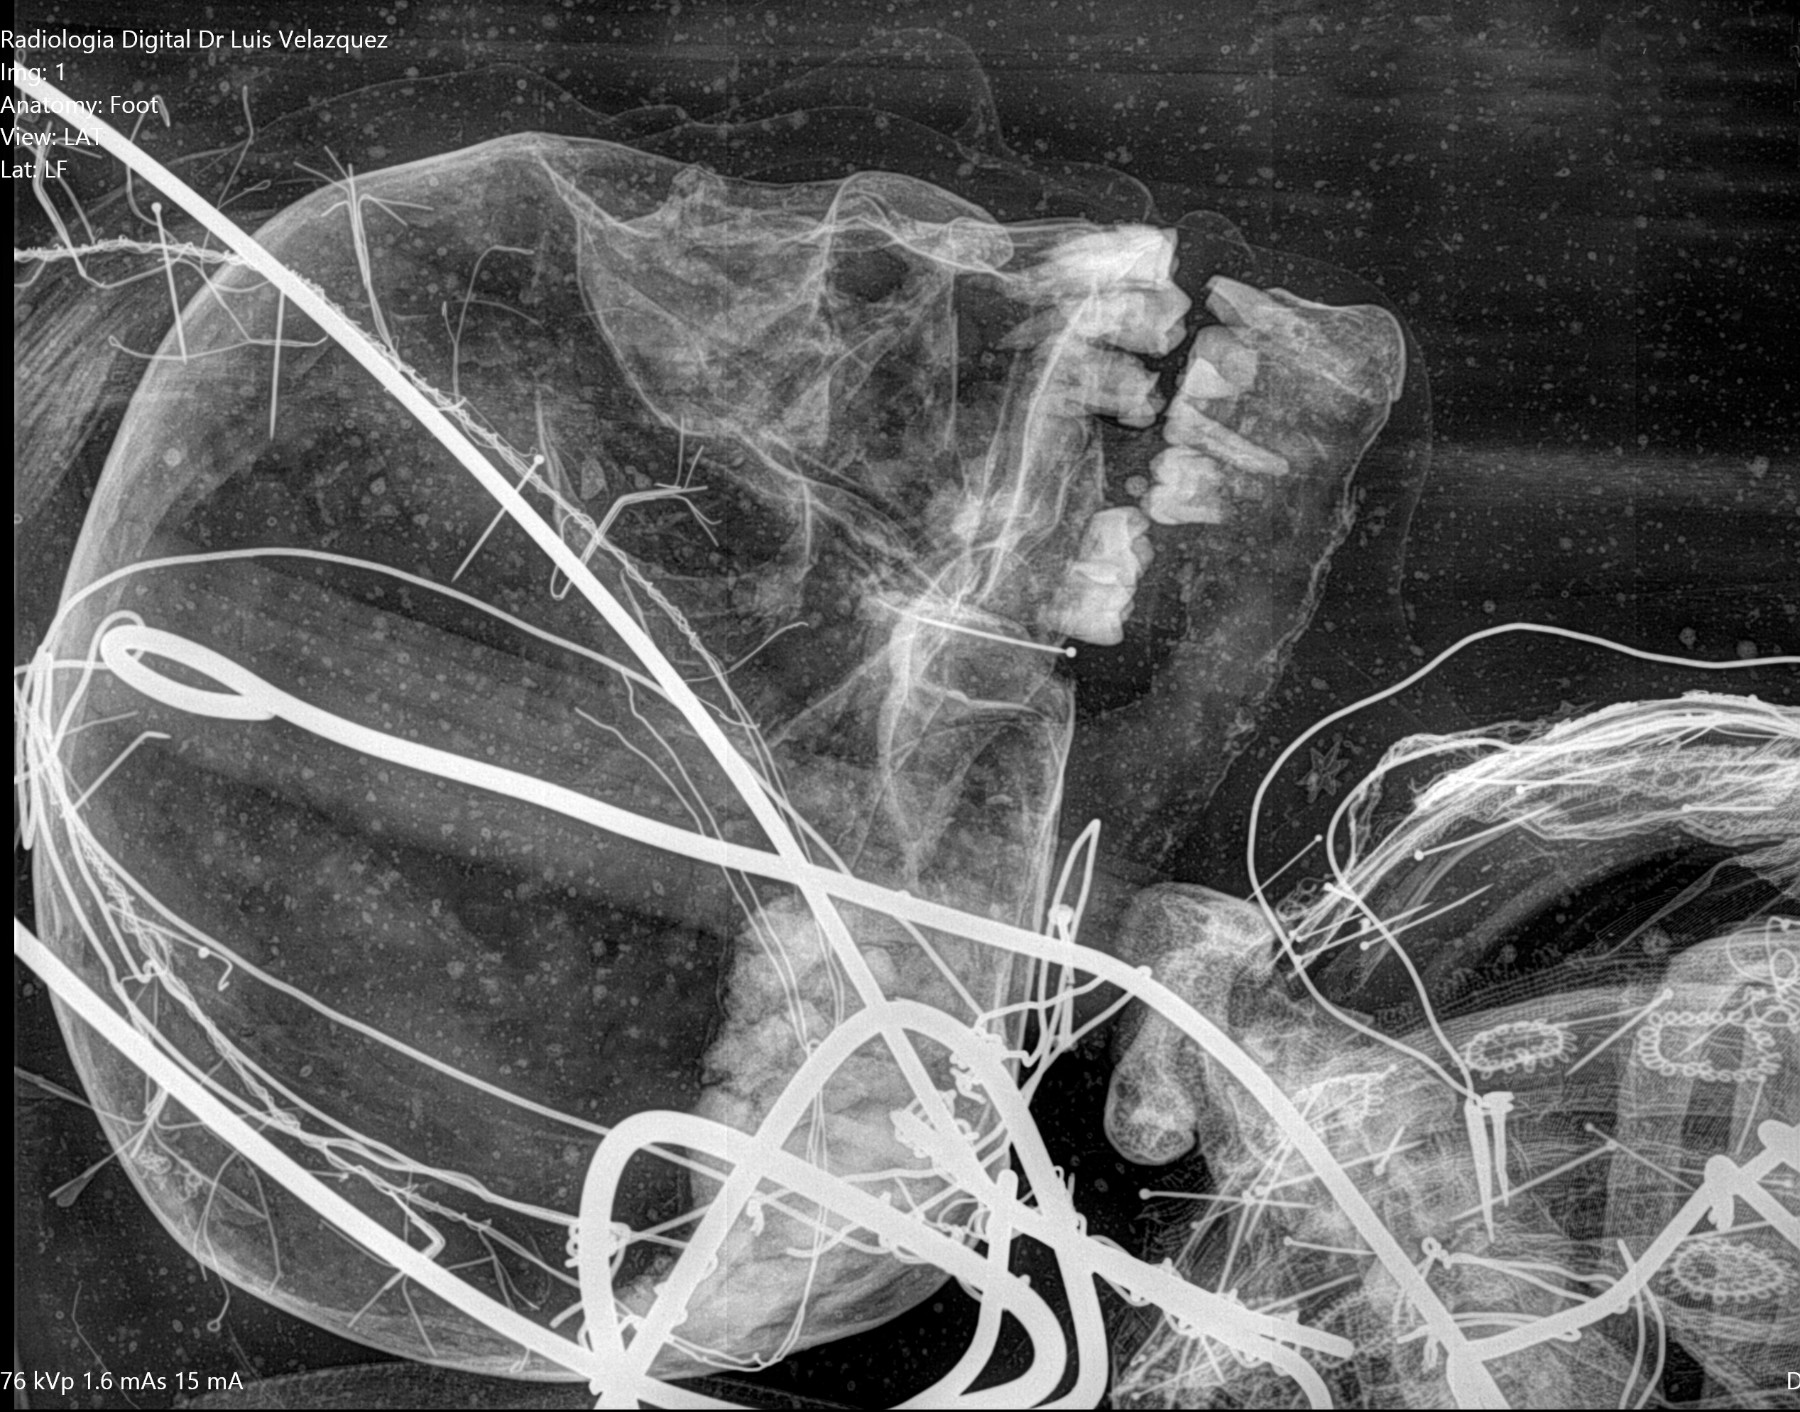

THE GENUS RHYNCHOTERIUM (MAMMALIA-PROBOSCIDEA) in the Hemphilliam - Blancan (NALMA) of central Mexico

In research in Neogene deposits from central Mexico, have collected abundant fossil materials, that have been referred to Rhynchotherium, based in not diagnostic materials and inaccurate age and locality, that not adequately di erentiate between the genus Rhynchotherium, Cuvieronius and Gomphotherium (Lucas y Morgan 2008).